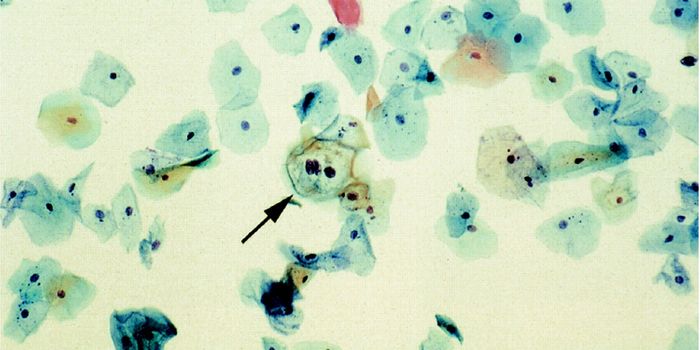

APR 15, 2015Health & MedicineMaking the decision to move from co-testing to primary Human papillomavirus (HPV) screening was one thing. Implementing ...

FEB 16, 2016Clinical & Molecular DXThe American College of Obstetricians and Gynecologists (ACOG) recently revised and updated its recommendations for cerv ...